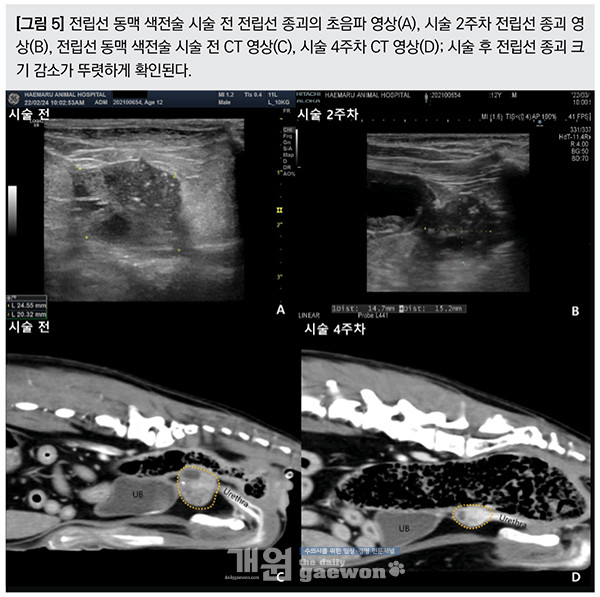

시술 2주차에 초음파 재검을 하였으며, 시술 직전 대비 전립선 크기는 약 45%(장축상 최대 면적 기준)가량 감소하였다.

시술 후 4주차 전립선 부피 평가를 위한 재검 CT 를 촬영하였으며, 부피 기준 60% 이상 크기 감소가 확인되었다[그림 5]. 현재 환자는 항암제를 vinblastine으로 변경하여 항암치료를 하고 있으며, 현재까지 유의적인 종괴 크기 증가 없이 잘 생활하고 있다.